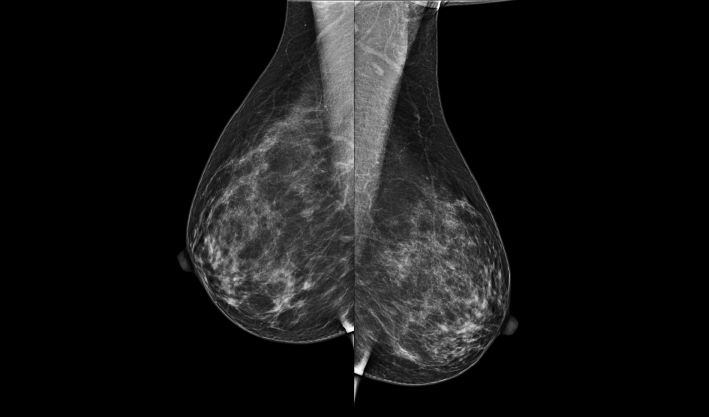

頭尾位(CC位) 內外斜位(MLO位) 補充體位(根據需求)

一鍵式視圖切換

致力于致密乳腺的早期癌變篩查和微鈣化簇精準定性。